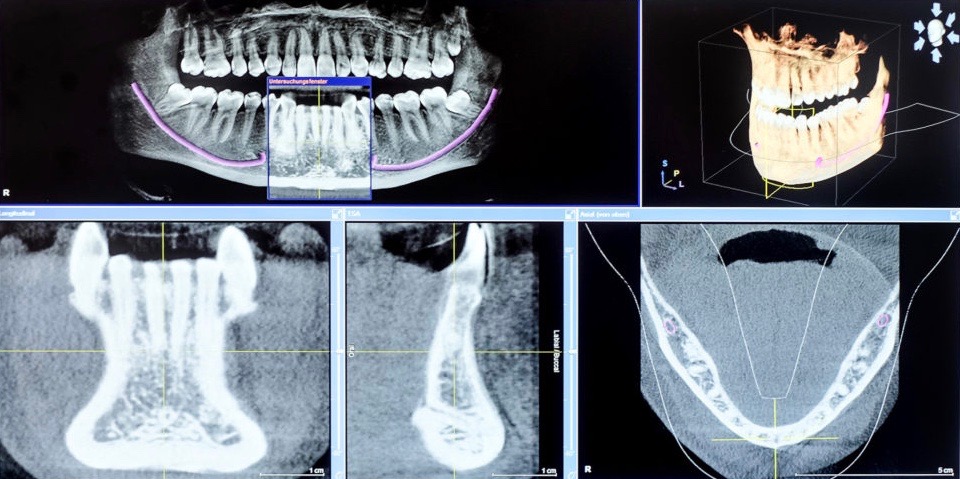

Eine vorliegende kritische Lagebeziehung unterer verlagerter Weisheitszähne zum Unterkiefernerv, als auch oberer Weisheitszähne zur Kieferhöhle ist in allen drei Ebenen darstellbar und die genaue Position der Zähne im Knochen bestimmbar. Gerade der Verlauf des Unterkiefernervs kann äußerst eng zu den Weisheitszähnen sein, sogar durch die Wurzeln dieser verlaufen. Je genauer der Behandler dies darstellen kann, desto eher ist eine mögliche Schädigung des Nervs bei der Entfernung des Zahnes vermeidbar. Gleiches gilt für verlagerte Zahnkeime an anderer Position, sowie mögliche Nichtanlagen von bleibenden Zähnen.

Bei krankhaften Prozessen innerhalb des Kieferknochens, wie z.B. Zystenbildungen, entzündlichen Prozessen an den Wurzelspitzen oder auch Abzessbildungen ist es ebenfalls möglich diese sowohl zuverlässiger darzustellen und somit auch zu befunden, als auch ihre genaue Lage dreidimensional exakt zu bestimmen. Ein Einsatz des DVT in der Zahnerhaltung ist ebenfalls möglich. Komplexe Wurzelanatomien mit unklarer Lage der Wunzelkanäle können die Voraussetzung für eine digitale Vomumentomographie sein. Es bietet sich somit die Möglichkeit, die genaue Lage, die Anzahl, die Anatomie und die Länge der Wurzelkanäle zu bestimmen und dadurch auch hier das Langzeitergebnis bzw. die Langzeitprognose erheblich zu verbessern.